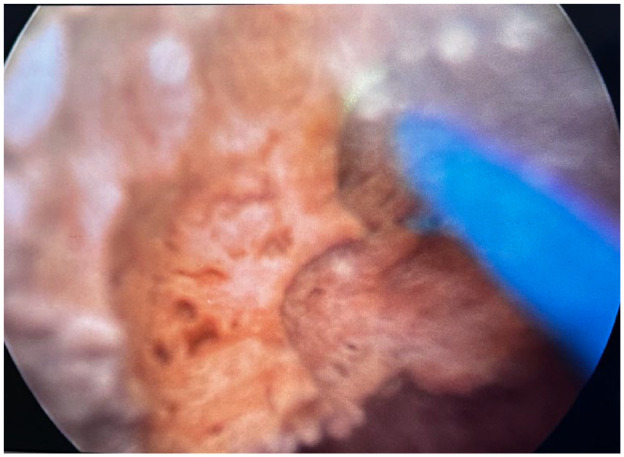

Case presentation: A 52-year-old woman patient arrived with acute urinary retention symptoms that lasted 6 hours. She complained of pain in the perineal and periurethral regions. She struggled with poorly managed type 2 diabetes, metabolic syndrome, and frequent cystitis. The examination showed the presence of a 2-cm stone in the urethra. The treatment utilised retrograde propulsion and laser fragmentation. Postoperative magnetic resonance imaging results were normal, and follow-up care involved managing diabetes and adopting lifestyle changes to prevent the recurrence of cystitis and stones for 6 months.